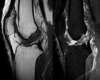

Selon le nombre des structures touchées et l’importance des lésions le chirurgien pourra définir s’il s’agit d’une entorse grave ou non. Il prescrira parfois un bilan complémentaire comprenant assez souvent une IRM du genou.

Cette IRM confirmera une éventuelle lésion du LCA et permettra de vérifier la présence de lésions associées sur d’autres ligaments et surtout sur les ménisques.